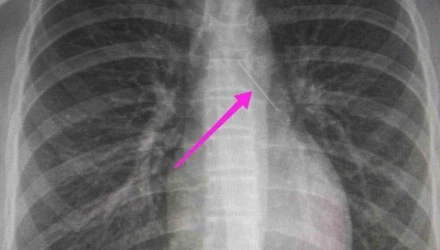

Από την απεικονιστική διερεύνηση που πραγματοποιήθηκε με ακτινογραφία θώρακος αρχικά και ακολούθως με αξονική τομογραφία θώρακος, διαπιστώθηκε η ύπαρξη αιχμηρού μεταλλικού ξένου σώματος στην αναπνευστική οδό (αριστερός κύριος βρόγχος) και όχι στην πεπτική οδό, αναφέρει η ανακοίνωση του νοσοκομείου, στα μέσα κοινωνικής δικτύωσης.